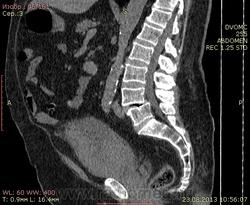

71 год. ЗНО мочевого пузыря. Куча сопутствующей патологии.

Исследование только в нативе. DICOM здесь http://files.mail.ru/33E39AFADBD643D6B6C470D5AD2350BE

Можно ли при таком исследовании говорить об инфильтративном росте(по состоянию околопузырной жировой клетчати и отсутствию четкого контура мочевого пузыря?).

Выраженный гидронефроз и гидроуретер справа говорит о прорастании в устье мочеточника, так?

Контуры мочевого пузыря нечеткие, размеры увеличены, содержимое неоднородное: от жидкостной до мягкотканной плотности, косвенные признаки инвазии устья правого мочеточника. Перивезикальныя клетчатка инфильтрирована. ЧЛС справа расширена, мочеточник справа расширен, с S- образным перегибом на уровне L4 позвонка. Диффузные инволютивно-атрофические изменения поджелудочной железы. Мелкие кистовидные изменения печени. Истинный антелистез L4 первой ст, ДОА правого тазобедренного IIIст, гемангиома тела L1.

В заключении стоит указать, что достоверность нативного исследования ОБП не высока. Косвенные признаки Са мочевого пузыря с инвазией устья правого мочеточника и правосторонним гидронефрозом. Цистоскопия нужна.

Это уже и мочевым пузырем не назовешь, потому как все стенки инфильтрированы местами даже с окружающим пузырным пространством(Cr).